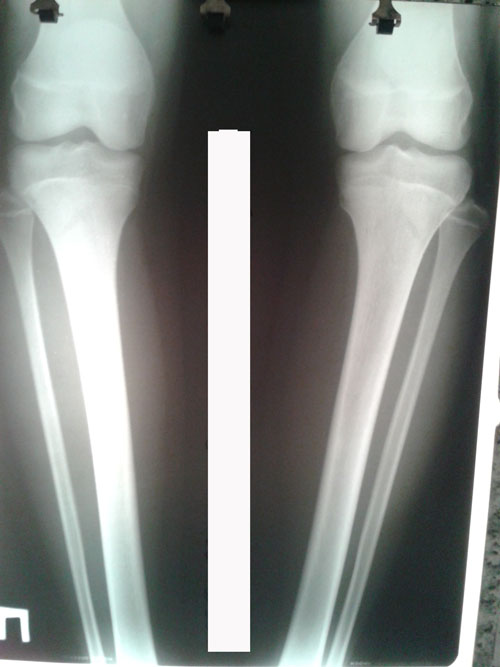

Рентген до операции.

20160709_130337.jpg